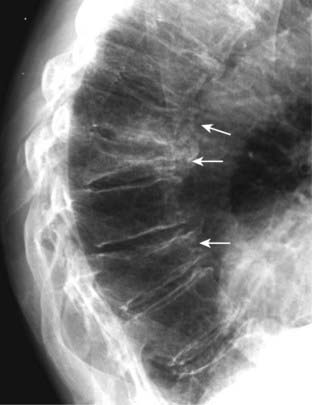

image Vertebral compression fractures are common, affecting women more than men, and typically secondary to osteoporosis. They may be asymptomatic or they may produce pain in the midthoracic or upper lumbar area that typically disappears in 4 to 6 weeks. Sometimes they are first noticed because of increasing kyphosis or loss of overall body height.

image Conventional spine radiographs are usually the study of first choice. MRI can be utilized for differentiating osteoporotic compression fractures from malignancy. Both MRI and nuclear bone scans can help in establishing the age of a compression abnormality that might be impossible on conventional radiographs alone.

imageOsteoporotic compression fractures usually involve the anterior and superior aspects of the vertebral body sparing the posterior body. There will usually be a difference in the height between the anterior and posterior aspects of the same vertebral body in excess of 3 mm. Alternatively, the compressed body is typically >20% shorter than the body above or below it.

image This compression pattern produces a wedge-shaped deformity that leads to accentuation of the normal kyphosis in the thoracic spine (the so-called dowager’s hump) (Fig. 24-10).

image There is usually no neurologic deficit associated with an osteoporotic compression fracture because the fracture involves the anterior part of the vertebral body, away from the spinal cord.

image

Figure 24-10 Compression fractures secondary to osteoporosis.

Vertebral compression fractures are common, affecting women more than men, and typically secondary to osteoporosis. Osteoporotic compression fractures usually involve the anterior and superior aspects of the vertebral body sparing the posterior aspect (solid white arrows). This produces a wedge-shaped deformity that leads to accentuation of the kyphosis in the thoracic spine. Progressive loss of overall body height is a common finding with compression fractures in the elderly.